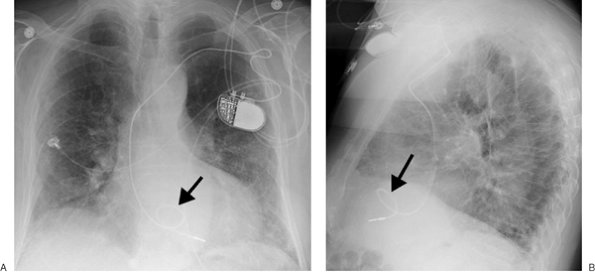

none should be present during diastole. If the catheter is short, dislodgment may occur, and the catheter may enter the right atrium, pulmonary artery, SVC, or coronary sinus. If the lead is too long, a bend in the wire may occur, causing lead fracture (Fig. 5-22). A redundant lead may also perforate the myocardium; this complication generally occurs at the time of or within a few days after insertion. The frontal or lateral radiograph will show the catheter tip outside or within 3 mm of the edge of the cardiac silhouette (Fig. 5-23). Perforation can lead to cardiac tamponade or postcardiotomy syndrome. Inflammation and infection can occur within the vein or the generator pocket; the latter occurs in up to 5% of patients (20). Major vein thrombosis and pulmonary embolism are additional complications of pacemaker insertion.

FIGURE 5-22. Looped pacer lead. PA (A) and lateral (B) chest radiographs show looping of the pacer lead over the area of the expected tricuspid valve (arrow). This positioning can result in dysrhythmia, lead fracture, or myocardial perforation.